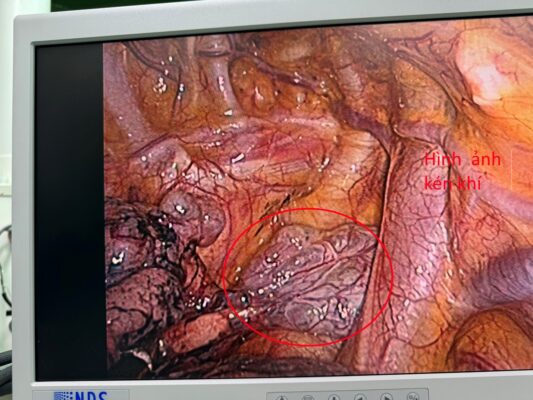

Bệnh nhân được tiến hành phẫu thuật cấp cứu dẫn lưu màng phổi phải tối thiểu. Sau dẫn lưu sinh hiệu ổn định, theo dõi không xuất hiện tràn khí thêm. Sau 03 ngày tiến hành kẹp ống dẫn lưu phát hiện tràn khí trở lại. Các bác sĩ khoa Ngoại chung nhận định đây là trường hợp TKMPTP nguyên phát mức độ nặng, điều trị bảo tồn không kết quả, quyết định phẫu thuật nội soi lồng ngực giải quyết triệt để nguyên nhân. Phẫu thuật quan sát thấy có tổn thương kén khí vùng đỉnh phổi phải, nhu mô phổi còn lại bình thường, tiến hành cắt kén khí, khâu tổn thương, đặt dẫn lưu màng phổi phải. Theo dõi sau 03 ngày tiến hành kẹp ống dẫn lưu, thấy phổi nở tốt, không có tràn khí tái phát, rút ống dẫn lưu. Theo dõi bệnh nhân sau rút ống ổn định, cho ra viện.

Hình ảnh kén khí thấy được khi thực hiện phẫu thuật